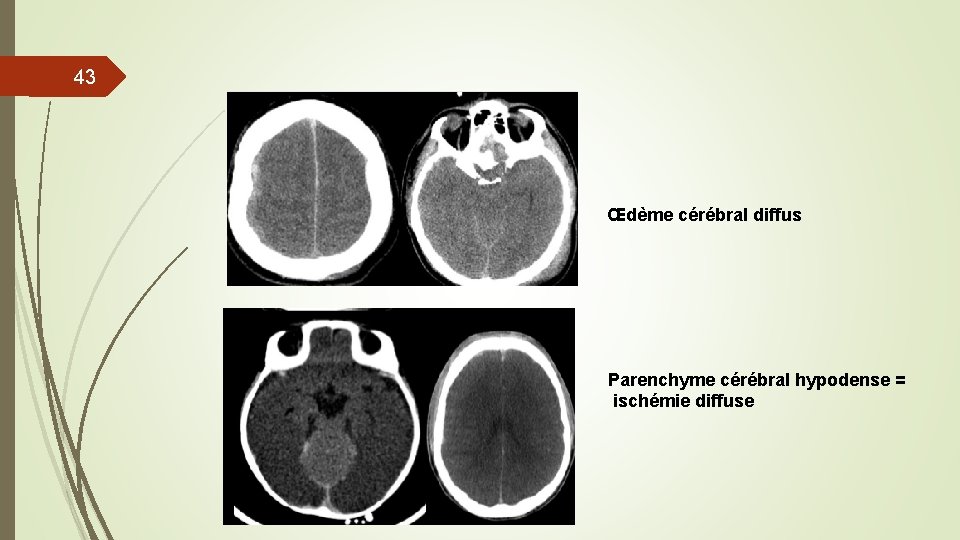

43 Œdème cérébral diffus Parenchyme cérébral hypodense = ischémie diffuse